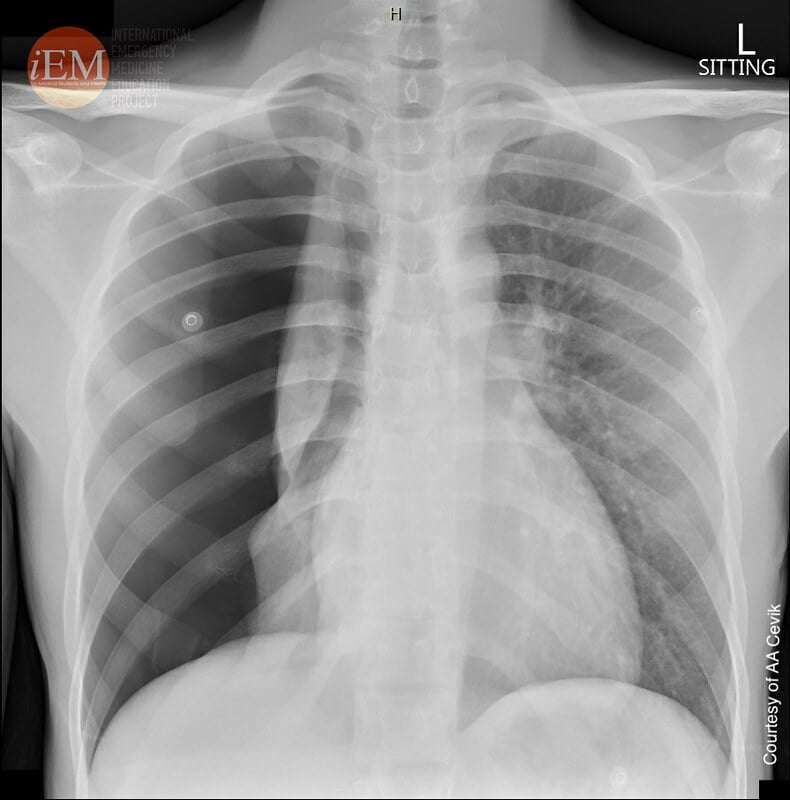

- Рентгенова снимка на гръдния кош: Въпреки че не се изисква рутинно, рентгенография на гръдния кош може да се направи, ако има съмнение за усложнения като белодробна пневмония, особено в случаите, когато състоянието на детето не се подобрява или се влошава прогресивно.